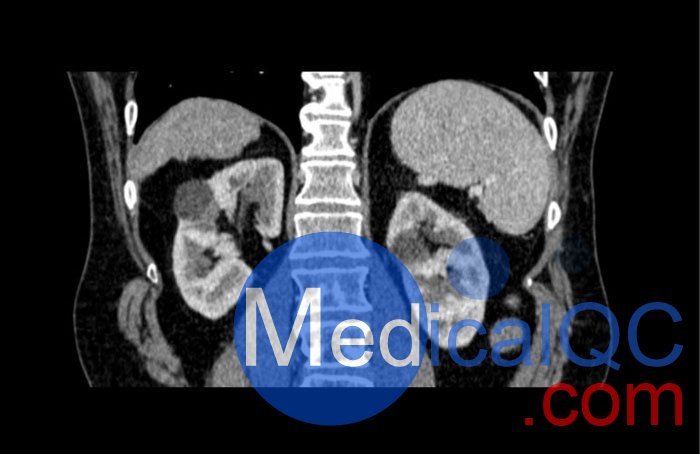

WEK53-04肝硬化腹部模體,WEK53-04腹部模體代表膽囊切除術(shù)后的腹部,帶有小夾子。肝臟有肝硬化的典型體征,在第三腰椎水平植入下腔靜脈過濾器。兩個腎臟都有囊性病變,左側(cè)有一小塊腎結(jié)石。

真實模擬脈管系統(tǒng)、骨骼和軟組織,包括肝臟、胰腺、脾臟、腎上腺、腎臟、胃、小腸和結(jié)腸。

• 腎囊腫

• 腎結(jié)石

SAG: